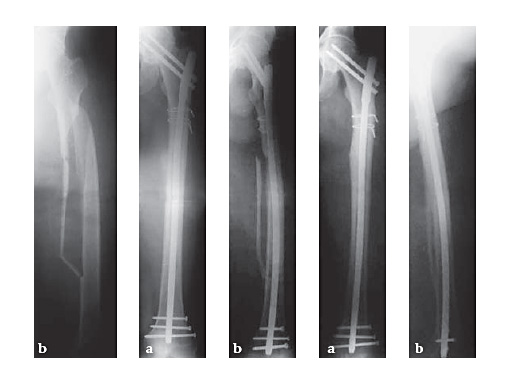

53-year-old malefallen in the busAO Classification 32-B1.1

Case provided by Hermann Bail, Berlin, DE